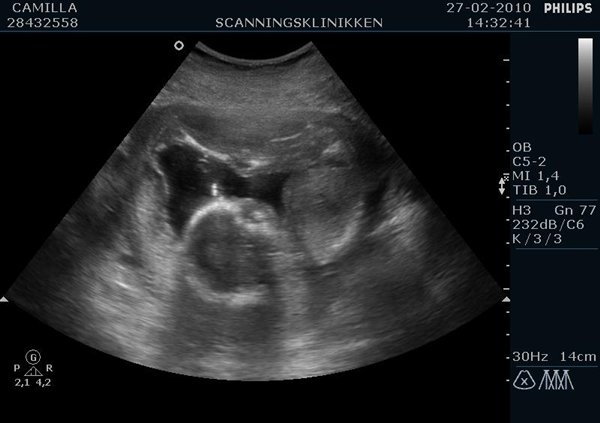

Ville lige ligge lidt billeder ind af min lille pige (Emilie?)  fra kønsscanningen igår

Vedhæftede fotos (klik for at se i fuld størrelse)

Billedet af hendes ædlere dele beviser 2stk skamlæber, (de to prikker)

Jordemoderen scannede mig fra alle leder og kanter og der var hverken tap eller pung at finde